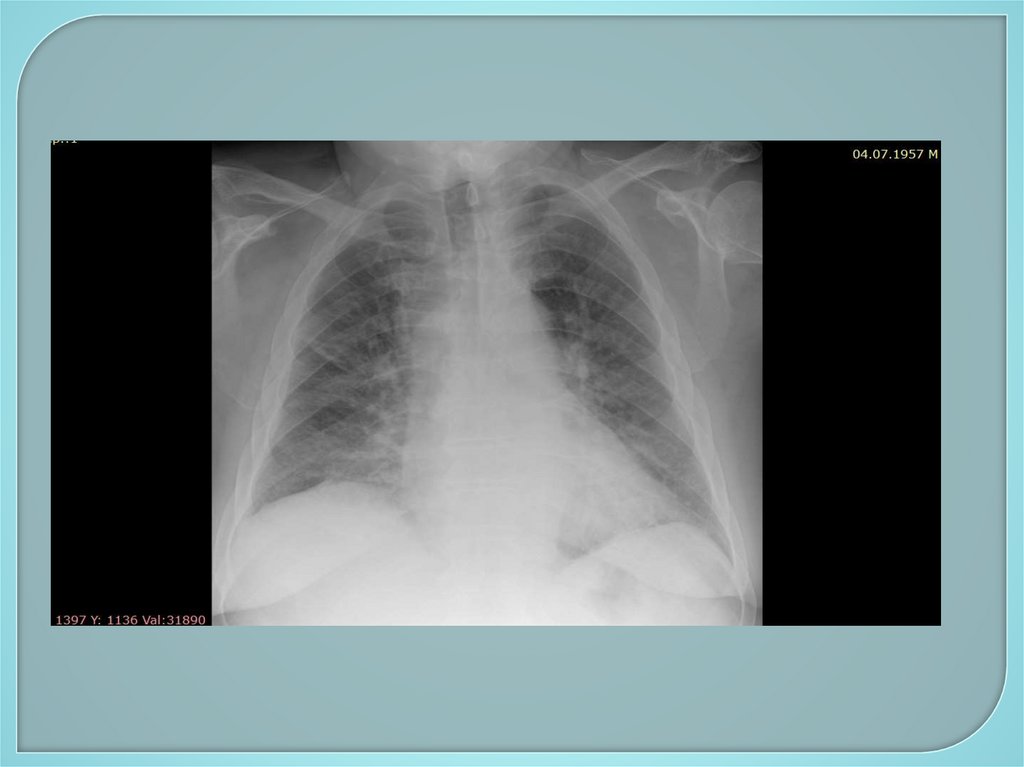

101. Дополнительное обследование

Инструментальные методы:

1. Рентгенологические методы –

рентгенография грудной клетки,

флюорография, бронхография,

компьютерная томография